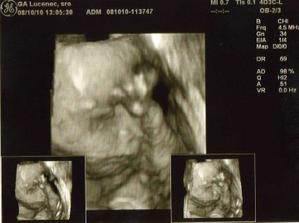

Nase 3D sono